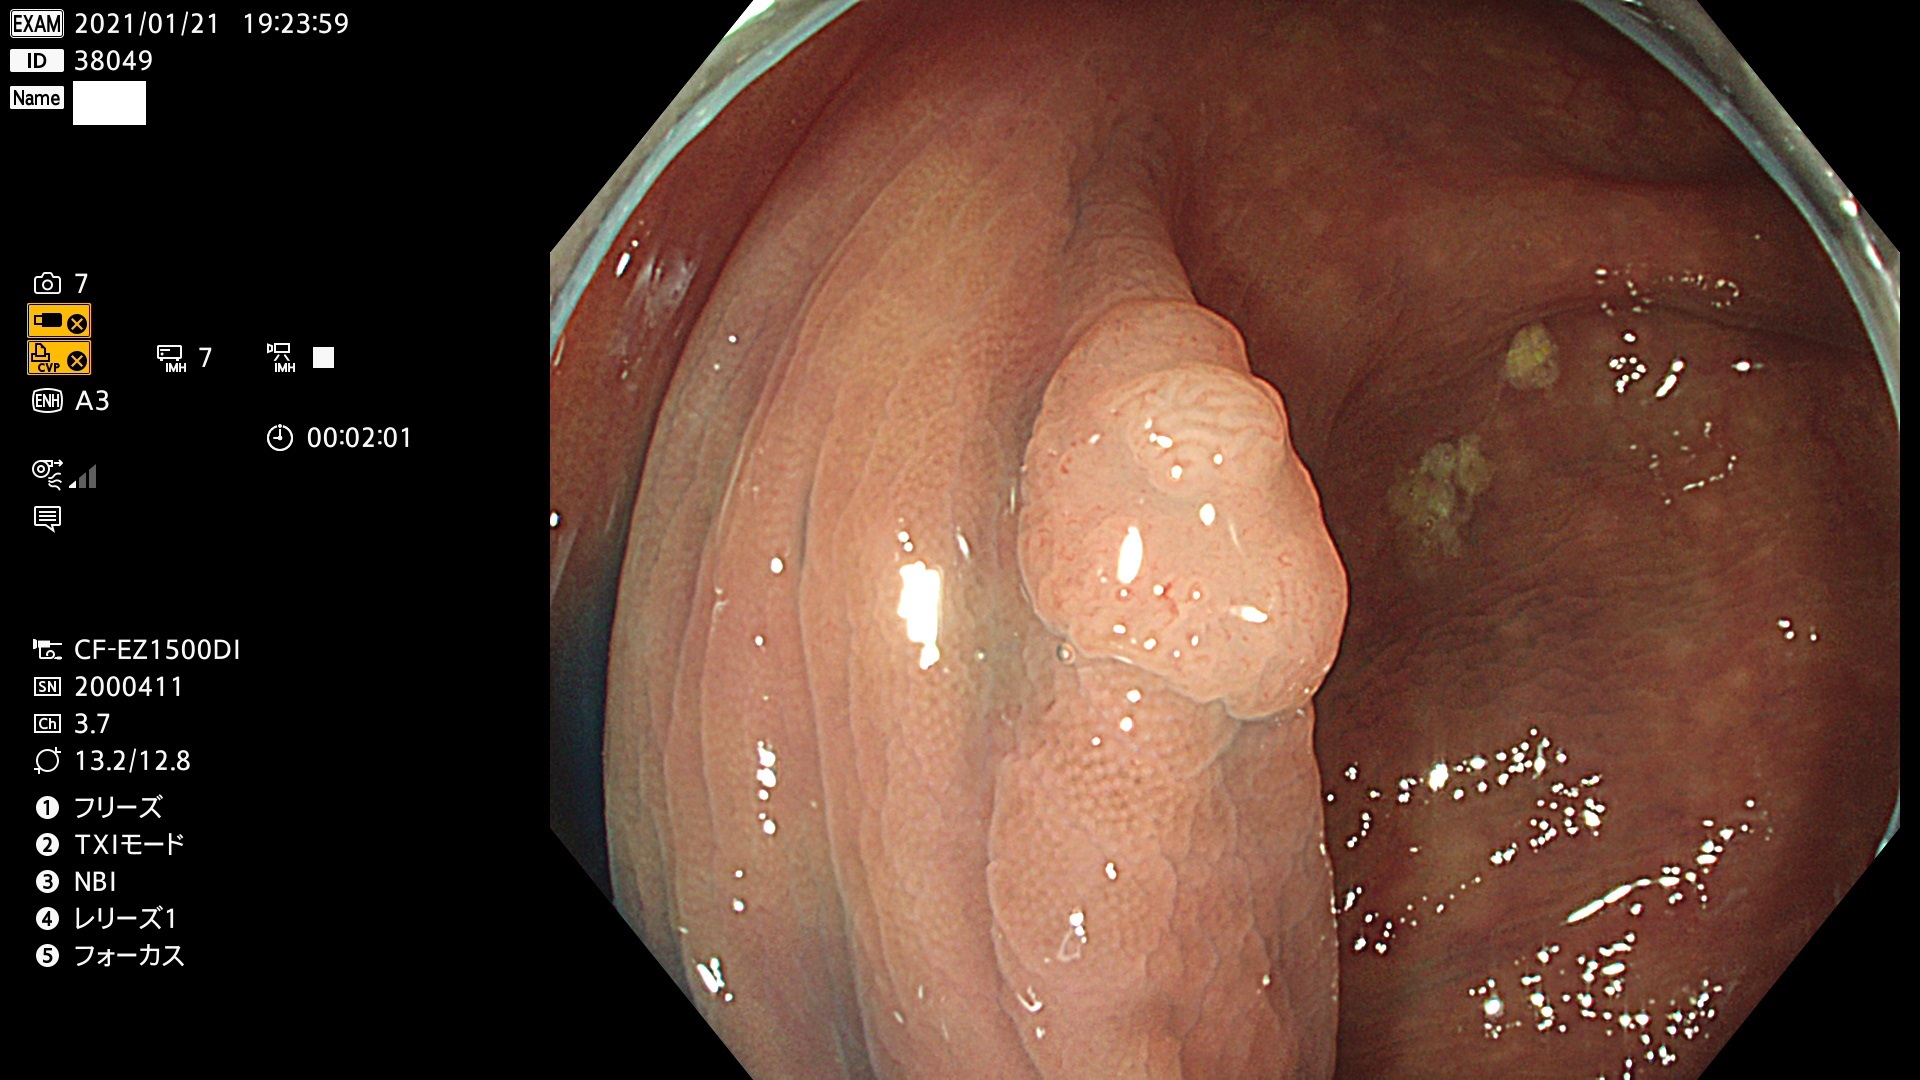

38001 38002 38003 38004 38006(SSAPのみ) 38007 38008 38009 38010 38012 38013 38014 38016 38018 38020 38021 38025 38026 38029 38032 38033 38034 38035 38036 38037(SSAPのみ) 38039 38043 38044 38048 38049 38050 38052 38055 38056 38057 38058 38059 38064(SSAPのみ) 38065 38068 38069 38070 38071 38072 38074 38075 38076 38078 38079 38080 38082 38083 38084 38085(SSAPのみ) 38086 38087 38088 38089 38090 38091 38092 38093 38094 38097 38098 38099

発見困難で危険性の高い平坦型病変(上記100名より抽出)